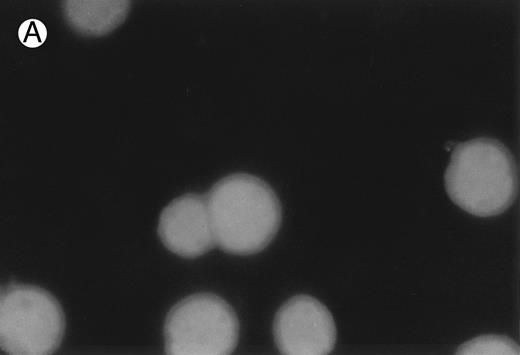

CD437 inhibition of HL-60R growth and induction of apoptosis.Although HL-60R cells are resistant to RA-mediated inhibition of growth,16,17 they are exquisitely sensitive to CD437-mediated inhibition of growth (Fig 1A) with as little as 25 nmol/L CD437 inhibiting growth by approximately 50% (Fig 1B). Similar inhibition of growth was noted in the parental HL-60 cell line (Fig 1C), as well as the RA-resistant K562 leukemia cell line28 (Fig 1D). As evidenced in Fig 1A, there was not only a total inhibition of cellular proliferation in the presence of CD437 but an actual cell loss. We therefore examined whether CD437 induced programmed cell death (apoptosis) in the HL-60R cells. That CD437 indeed induced apoptosis in the HL-60R cells was documented using three independent parameters. (A) HL-60R cells after exposure to 1 μmol/L CD437 displayed marked nuclear fragmentation and chromatin condensation, with the nuclear and cytoplasmic membranes remaining intact (Fig 2), a morphology indicative of apoptosis.29 (B) Incubation of HL-60R cells with 1 μmol/L CD437 resulted in internucleosomal cleavage and laddering of the DNA on gel electrophoresis (Fig 3), a hallmark of apoptosis.29 (C) A number of studies have suggested a critical role for cysteine proteases in the apoptotic process.30-37 Numerous substrates for this family of proteases have now been identified.37-41 PARP, which plays an important role in both DNA synthesis and repair, is cleaved early in the apoptotic process.37 38

CD437-induced apoptosis in HL-60R cells. HL-60R cells were grown as described in the Materials and Methods and exposed to either vehicle alone or CD437 (1 μmol/L) for 24 hours and then stained with aciridine orange. (A) Cells exposed to only vehicle. (B) Cells exposed to CD437 (1 μmol/L).